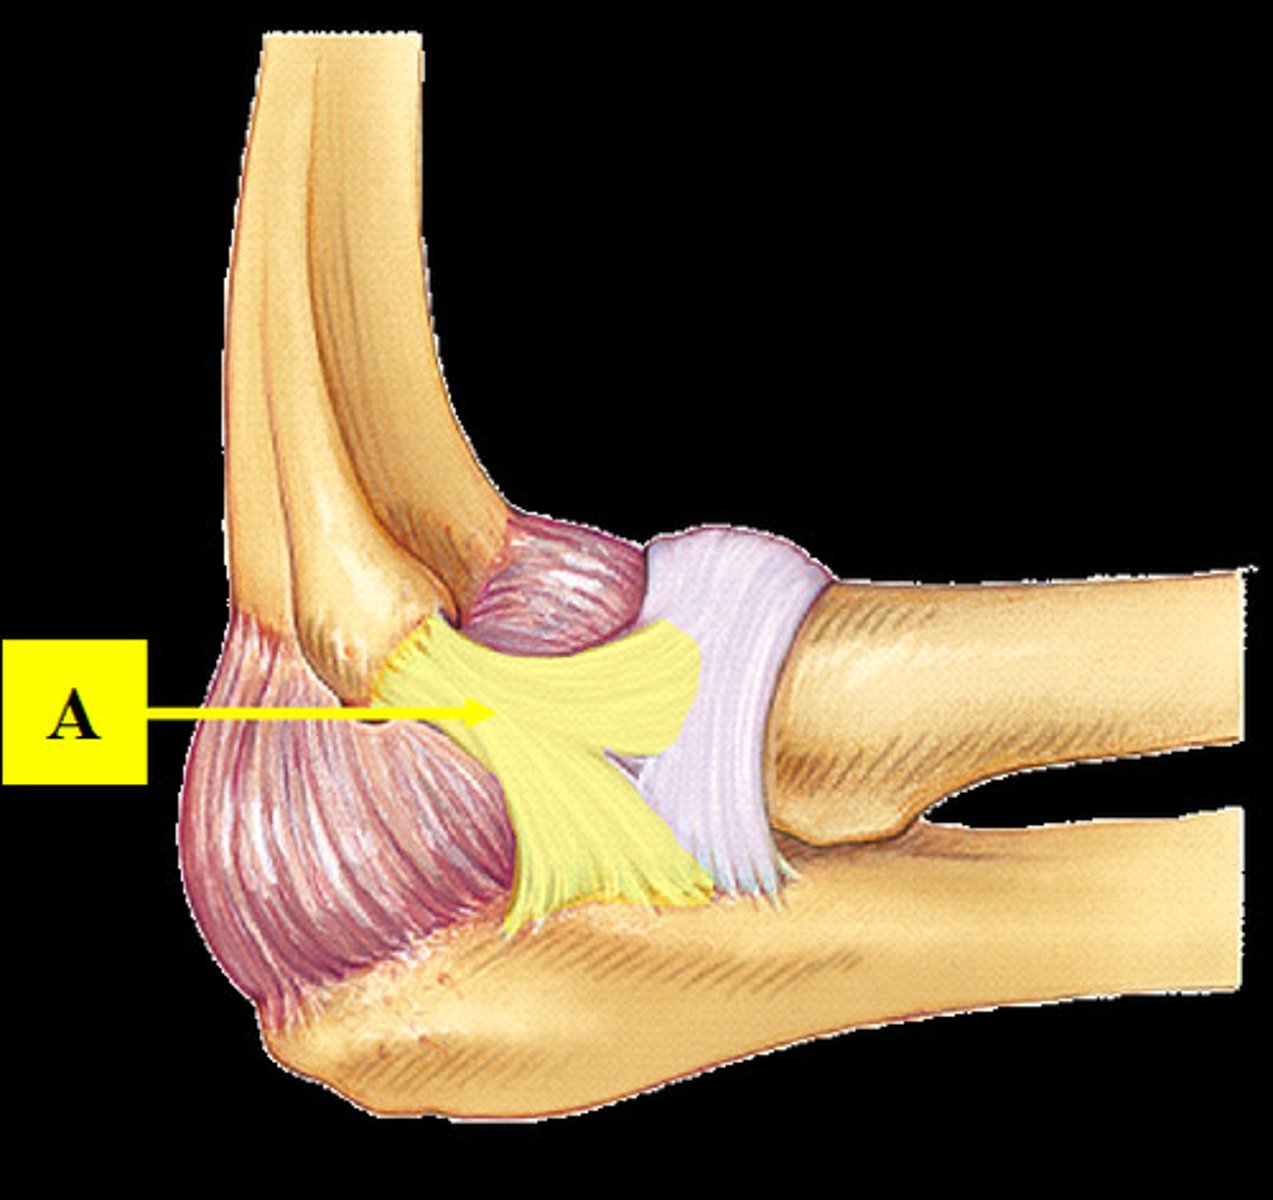

Radial collateral ligament

Anular ligament

Ulnar collateral damage